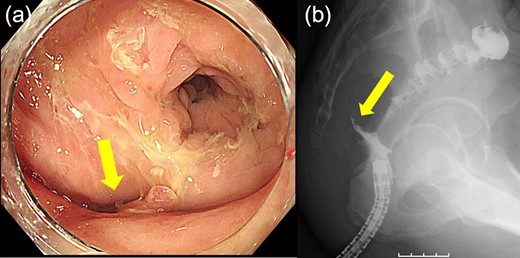

Case 1 was a 71-year-old man with a BMI of 29.7 kg/m2. Laparoscopic low anterior resection (LAR) and ileostomy was performed for rectal cancer in 2017 years. Postoperative fever and lower abdominal pain were noted, and colonoscopy was performed, and anastomotic leakage was noted with a correction of about 1/2 around the 6 o’clock direction of the anastomotic region, and fistula and formation of a large abscess cavity. After identification (Fig. 1), a tube was inserted for drainage and conservative treatment was performed. The patient was discharged on POD 46. Four months after the operation, marked improvement in the abscess cavity was noted but still remained (Fig. 2a and b). Anastomotic leakage was almost improved by colonoscopy at 17 months after surgery, but at the preference of the patient we performed colostomy 22 months after surgery (Fig. 3). It took a long time to improve intestinal movement of the colon because the large intestinal tract had not been used for a long time, and conservative treatment was performed using a nasogastric tube for paralytic ileus. Diet was initiated 7 days after surgery, and the patient was discharged from the hospital 14 days after surgery. The Wexner score [2] was 19 points one month after closure, 17 points 3 months after the operation and 16 points after 6 months after the operation, and severe anal dysfunction was observed, but gradually improved.

(a) Colonoscopy shows a fistula (arrow). (b) Enema examination shows a cavity (arrow) leading from the fistula.